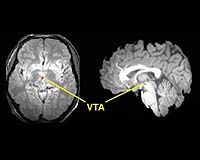

Horizontal (left) and vertical (right) slices of brain show increased blood flow (red region) in brainstem (VTA or ventral tegmental area) in measurements made by functional magnetic resonance imaging. Credit: Princeton University

A team of scientists from Princeton University has devised a new experimental technique that produces some of the best functional images ever taken of the human brainstem, the most primitive area of the brain.

Reporting in the Feb. 28 edition of Science, the scientists describe using functional magnetic resonance imaging to study brainstem activity in dehydrated humans. The scanning technique allows researchers to watch the brain in action.

The team was able to develop high-resolution images that tracked the activity of tiny clusters of dopamine neurons. They weeded out distortions caused by many pulsing blood vessels in the brainstem. They also employed computerized rules of thumb known as algorithms and imaging techniques to reduce the effects of head movement and combine images from different subjects.